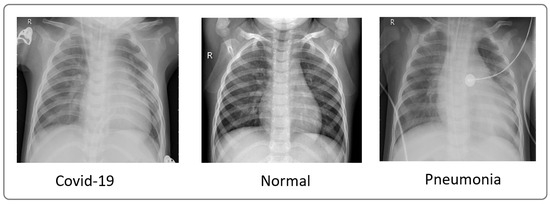

To evaluate our model, we utilized X-ray images from COVID-19 patients sourced from multiple datasets, including hospital data related to the COVID-19 outbreak [15,16] and Kaggle data [16]. We considered two datasets. The first one comprised 4050 images, with 3000 images for training and 1050 images for testing. The second one comprised 6378 images, with 4878 images for training and 1500 images for testing. These datasets included images from confirmed COVID-19 patients, normal individuals, and pneumonia patients. Figure 3 showcases a sample of X-ray images from these datasets.

Figure 3. Sample of images from the dataset used [16].

Utilizing the dataset showcased in Figure 3, our model achieved an exceptional precision of over 98.8%, surpassing that of ResNet50 (60%), Xception (86.74%), and VGG-16 (92%), as highlighted in Table 5. The confusion matrices presented in Figure 5, Figure 7 and Figure 9 further underscore the superior performance of our model compared to Xception.